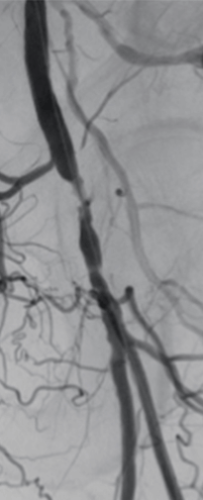

Passeo™-18 Lux™ in Action

REACT strategy: Treating Long SFA Occlusions with a Single Long-Length Drug-Coated Balloon (DCB) + Bare-Metal Stent (BMS)

Patient history

An 81-year-old woman presented with claudication of the right leg.

Procedure summary

Angiography showed a flush occlusion at the bifurcation between the deep femoral artery (DFA) and superficial femoral artery (SFA). After crossing, control angiography showed a diffuse, sub-occlusive long SFA lesion (Figure 1).

Pre-dilatation was performed with plain angioplasty balloon. Next, one long-length Paclitaxel-coated Passeo™-18 Lux™ DCB (6 x 200 mm) was inflated for three minutes to treat the segment, followed by a Pulsar™-18 T3 BMS.

Results

The final angiography showed complete revascularization of the femoropopliteal segment (Figure 2).